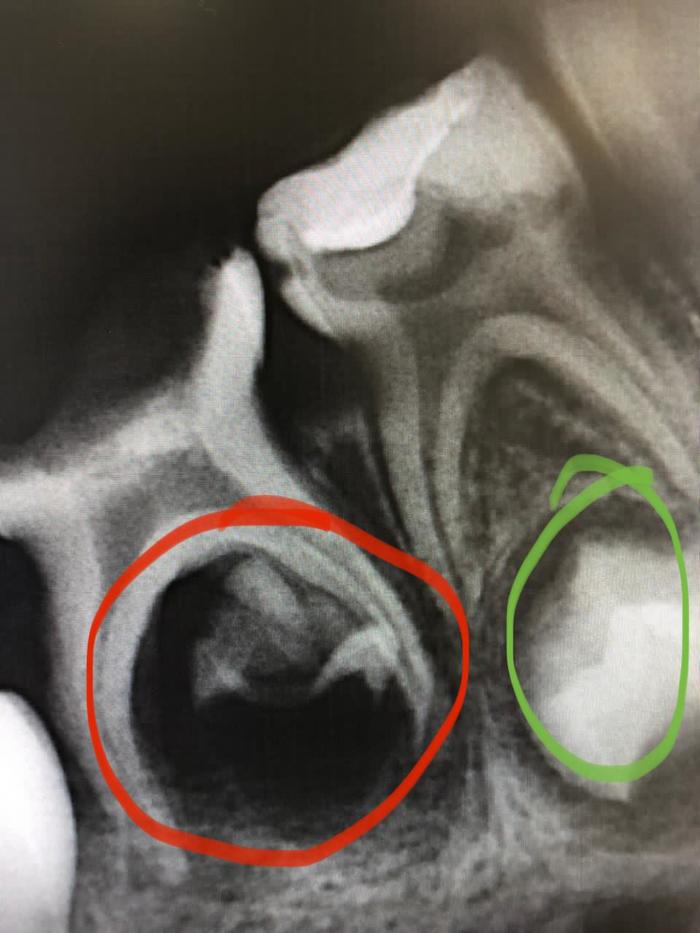

Сегодня расскажу следующую историю: на прием к стоматологу пришла мама с ребенком 5 лет, с жалобами на зубную боль. До этого, год назад они лечили зубы в наркозе в другой клинике (к нам часто приходят переделывать их работы, там дешевле). На рентген картине мы видим следующее:

Сейчас все объясню: на снимке два молочных зуба, под молочными зубами находятся зачатки постоянных зубов (как в зеленом кружочке). То что отмечено красным это погибший зачаток, инфекция с молочного зуба спустилась вниз, и убила его. По итогу у ребенка никогда не вырастет постоянный зуб!

Таких примеров очень много! Родители, которые думают зачем лечить молочные зубы, ау!! "Сами выпадут/ выдернем как сгниют". Потом можно забыть о нормальном прикусе, брекеты и импланты обеспечены.. О последствиях отсутствующего зуба можно много говорить, поэтому призываю Вас водить детей для осмотра, а не когда уже началась боль и процесс воспалительный. Так Вы приучаете детей не бояться, здоровья Вам, оно очень дорого стоит..